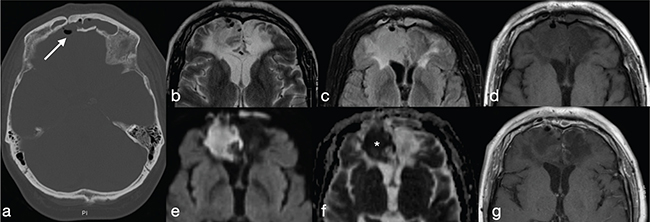

Early cerebritis is seen as a nonspecific focus of oedema with or without contrast enhancement. It appears as an ill-defined area, hypointense on T1-weighted images (wi) and hyperintense on FLAIR and T2-wi. Using DWI may help to differentiate cerebritis from other lesions as it shows restricted diffusion (i.e., low signal in apparent diffusion coefficient-ADC) (Figure 1). Mature pyogenic BAs usually are round or oval-shaped with a central cavity filled with pus, hypointense on T1-wi and hyperintense on T2-wi.

FIG 1. Early Cerebritis in a 57-Year-Old Man who Presented with Headache, Fever and Lethargy after a Previous History of Motorcycle Accident. (a) Brain CT shows post-traumatic sequelae in the basifrontal areas with a defect in the posterior wall of the right frontal sinus and associated pneumocephalus (arrow); within the wider ill-defined area of parenchymal contusion (b–d, g), an area of restricted diffusion (e–f) with no contrast-enhancement (g) consistent with early cerebritis, is shown.